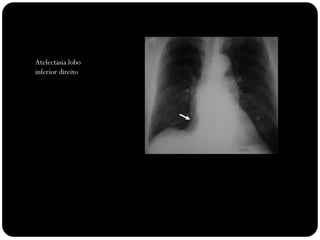

Atelectasia lobo

inferior direito

Observar:

Sinal de Luftsichel

Elevação

hemidiafrgma

esquerdo

Sinal da silhueta

(língula atelectasiada

também)

Atelectasia do lobo

inferior esquerdo

Atelectasias de lobos

inferiores deslocam

o hilo posterior e

medialmente;